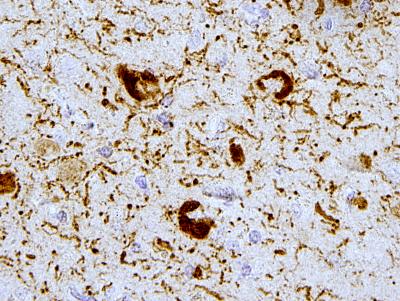

PHILADELPHIA – Researchers at the University of Pennsylvania School of Medicine have determined that a well-known chemical process called acetylation has a previously unrecognized association with one of the biological processes associated with Alzheimer's disease and related disorders. The findings were published in the latest issue of Nature Communications.

Tau is one of the primary disease proteins associated with a suite of neurodegenerative diseases. Tau proteins are expressed primarily in the central nervous system where they help with the assembly and stability of microtubules, protein structures that are the backbone of the nerve-cell communication system.

"Acetylation was only detected in diseased brain tissue from patients with Alzheimer's disease or frontotemporal degeneration, suggesting it may have a role in tau transformation linked to disease onset and progression," says senior author Virginia M.-Y. Lee, PhD, director of Penn's Center for Neurodegenerative Disease Research. "This suggests that one type of acetylation is a potential target for drug discovery and biomarker development for Alzheimer's and related tauopathies."

The researchers demonstrated that tau acetylation led to a loss of one of its major functions - to promote microtubule assembly, in addition to gaining a toxic function, pathological tau aggregation. Mass spectrometry analysis identified specific acetylation sites in the tau protein sequence that overlapped with known microtubule binding sequences, so acetylation may also play a role in faulty binding of tau to microtubules.

How normal tau becomes disengaged from microtubules to form disease-related clumps remains unknown. This study shows that acetylation is most likely another chemical modification implicated in neurodegenerative disorders to be explored as a potential way to detect and fight brain disease.